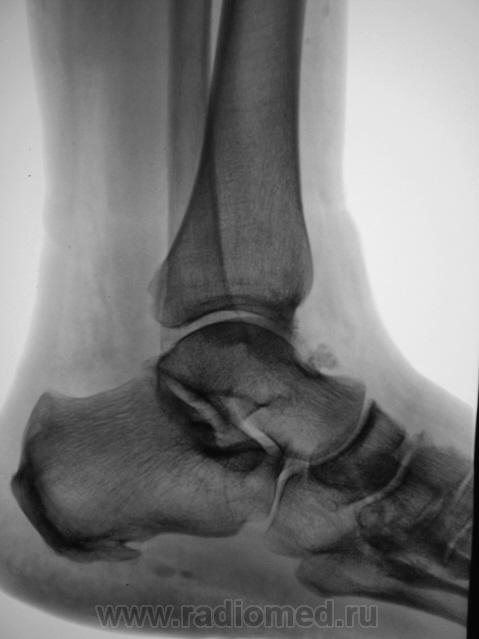

Трах... и вырос "грибок" на таранной...

Грибок этот не "трахогенной" природы. У меня вообще сомнения, что это вырост кости.

Понятно конечно, что "грибок" случайная находка. Но травма была...

Лодыжка срастется, никуда не денется. А вот оссифицирующий апоневрозит и данный то-ли экзостоз, то-ли оссификат капсулы будут периодически доставать и пациента, и врача-куратора.

Больше склоняюсь к хондромному телу, хоть в данном месте не встречал

Грибок этот не "трахогенной" природы. У меня вообще сомнения, что это вырост кости.  +1 !     Больше похоже на обызвествление сосудов . А хондроматоз - не подходит по локализации , хотя сама тень похожа внешне .